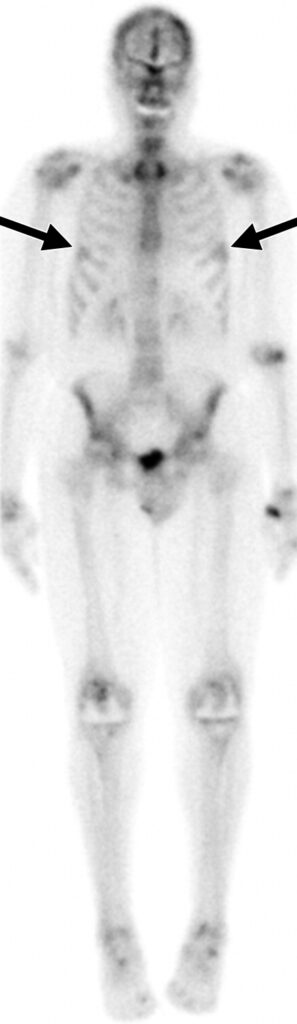

Uomo di 72 anni con artrite reumatoide sieropositiva (in terapia biologica) e dolore cervicale. Un iniziale reperto RM aveva posto il sospetto di un’infezione a livello dell’articolazione atlanto-assiale. Il paziente è stato sottoposto a scintigrafia ossea trifasica con 99mTc-MDP.

L’immagine whole-body di blood-pool (a) ha mostrato un aumentato accumulo del tracciante in entrambe le articolazioni delle spalle, nell’articolazione sternoclaveare destra, in entrambi i polsi, nel ginocchio destro e nelle piccole articolazioni di mani e piedi. L’immagine whole-body tardiva (b) ha evidenziato un’aumentata concentrazione del tracciante nelle medesime regioni che mostravano un aumentato accumulo ematico. La SPECT-TC della regione testa-collo ha mostrato un’aumentata captazione del tracciante lungo le faccette di sinistra tra le vertebre C1 e C2 (c) e nell’articolazione sternoclaveare destra (d), quadri interamente riconducibili ad artrite reumatoide attiva.